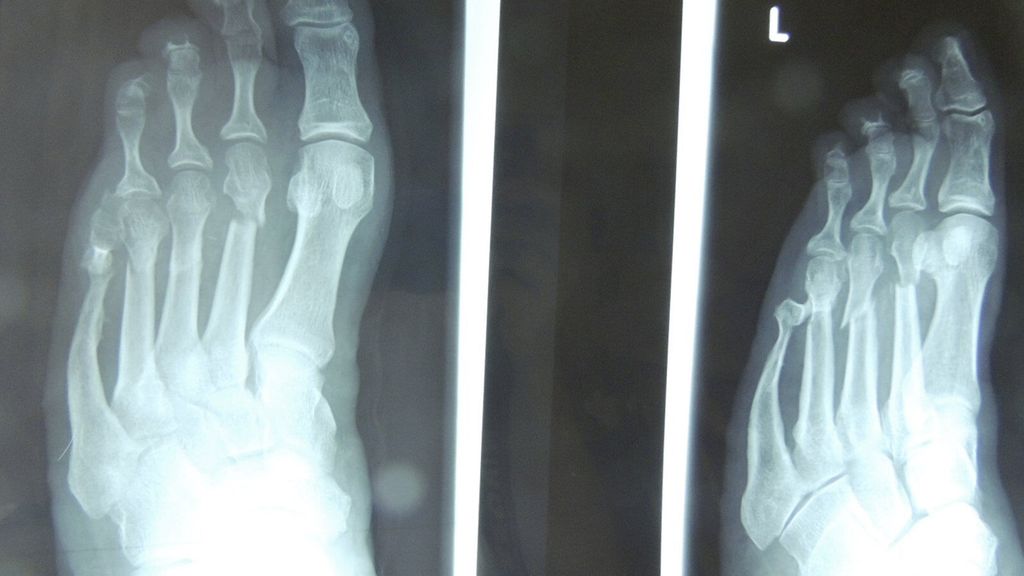

Hier haben die minimalinvasive Vorfußchirurgie im Sinn von verkürzenden elevierenden Metatarsale-Osteotomien (DMMO) und auch Zehenosteotomien samt Tenotomien sowie das minimalinvasive Abtragen von Exostosen eine große Bedeutung erlangt (Abb. 1,2).

Abb. 1: Malum perforans mit Knochenkontakt (a), minimalinvasive Chevron-/Akin(MICA)-Osteotomie (b), 2 Wochen postoperativ (c), nach 4 Wochen abgeheilt, kein Rezidiv (d), postoperatives Röntgen, 2 Wochen Gips mit Belastung (e)

Abb. 2: Malum perforans nach 18-monatiger Therapie (a), postoperatives Röntgen nach Osteotomie (b), 6 Wochen postoperativ, Narbe 1 cm (c, d)